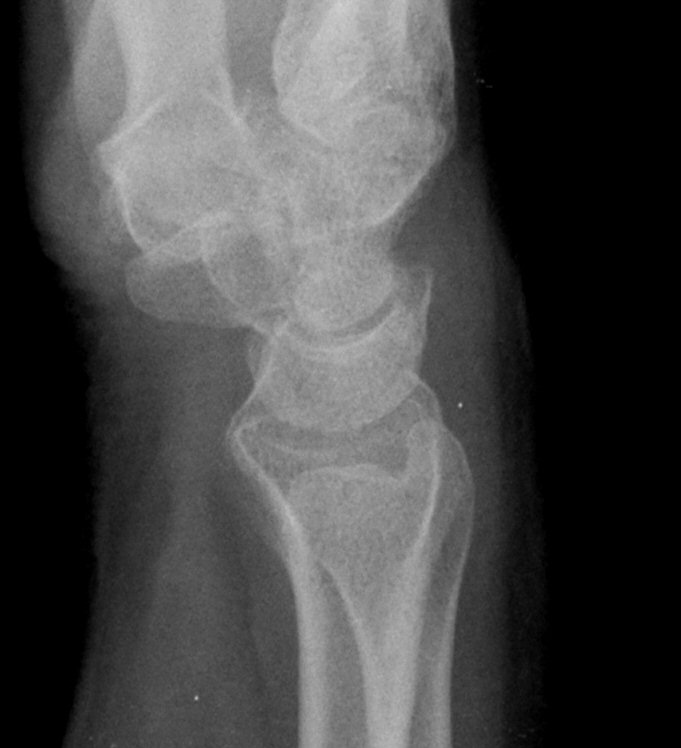

´Ü¼ø¹æ»ç¼±°Ë»ç

ƯÀÌ ¼Ò°ß ¾øÀ½(÷ºÎ ÆÄÀÏ)